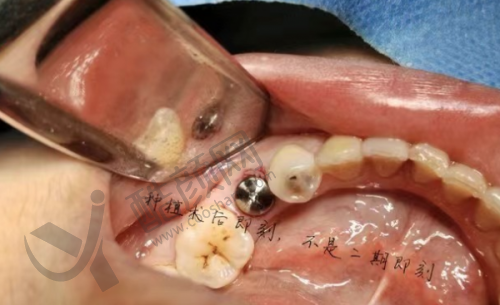

史衡涛医生在种植牙领域有着深厚的造诣,其技术水平非常可靠。他擅长全口种植牙、半口种植牙、单颗种植、多颗种植以及即刻种植牙等多种种植技术。在临床实践中,面对不同患者复杂的口腔状况,他都能精细分析并制定出更适合的种植方案。

他致力于为患者提供无疼痛的种植牙体验,采用微创技术来减少手术带来的不适。许多患者反映,在他的治疗下,不仅手术过程顺利,而且修养期也相对较短,极大地减轻了他们的痛苦。他还积极应用临床新技术,尤其是在微创保护性修复方面,他的研究成果得到了同行的高度评价。